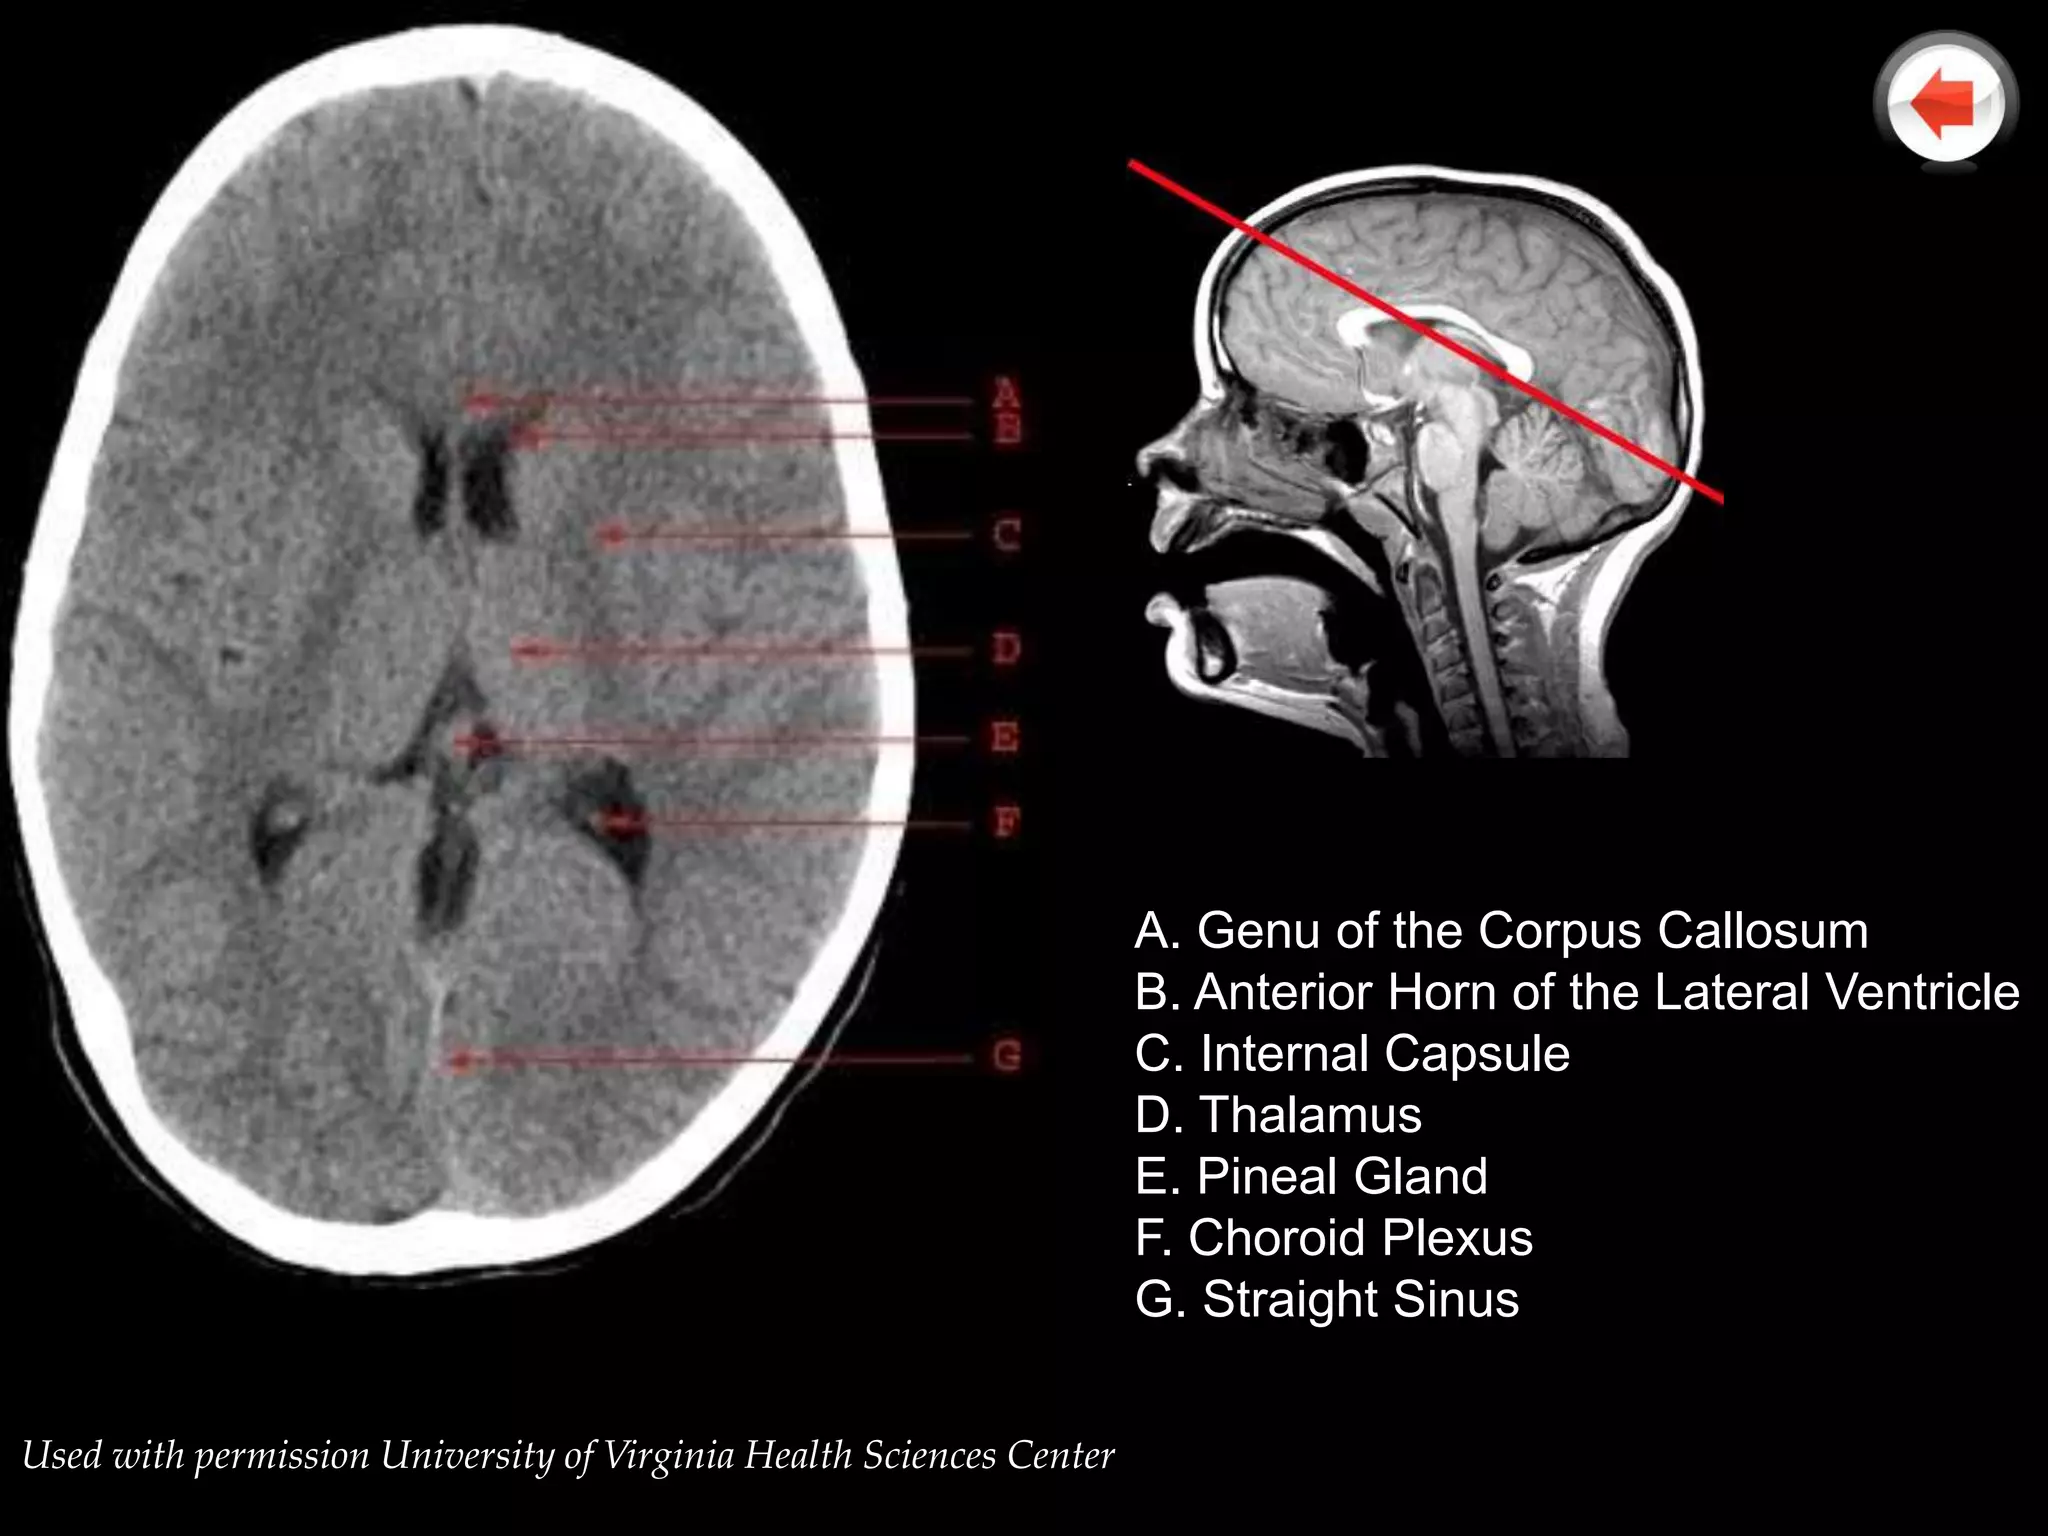

A. Genu of the Corpus Callosum

B. Anterior Horn of the Lateral Ventricle

C. Internal Capsule

D. Thalamus

E. Pineal Gland

F. Choroid Plexus

G. Straight Sinus

Used with permission University of Virginia Health Sciences Center